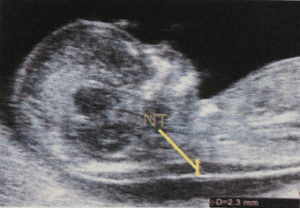

正常胎児にもみられる検査所見ですので、形態異常とは別に考えます。ダウン症候群(21トリソミー)では初期の超音波マーカーでNTと呼ばれる胎児後頭部の皮下浮腫の厚さを測定する検査としておこなわれています。この検査は、出生前診断検査の一つでもあり非確定的検査のひとつです。

NTとは首の後ろの皮下の厚さをを見る検査です。すべての胎児にあるもので、NTが厚くても胎児が正常か異常かの判別をすることはこの検査だけではできません。また、NTの厚さは胎児の大きさにも関係するので、正確な胎児の頭殿長の測定も重要になります。

NTは妊娠初期の限られた時期(11週~13週)に正常・異常に関わらず胎児にみられる所見です。NT自体が、病気というわけではなく妊娠初期特有の胎児の生理的な変化なのです。はじめは肥厚していても週数とともに目立たなくなったり、消失することも多いのです。たとえNTの肥厚が見られたとしても染色体異常疾患とは限らず先天性の心疾患や骨などの疾患が潜んでいる場合もあります。また、NTだけでなく、鼻骨・三尖弁血流・静脈管の血流などの検査も組み合わせておこなう場合もあります。

3.5mm未満といわれています。基準値に従って正確に測定されたNTが6mmあったとしても元気な赤ちゃんである確率は50%あります。